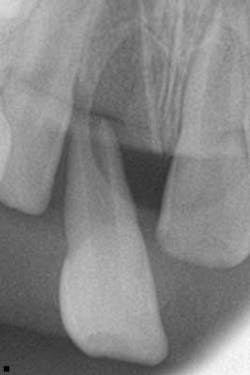

A healthy 7-year-old female presented directly from school with her father stating that she fell off the monkey bars. This was her first visit to the dentist. Initial exam revealed that tooth No. 8 was partially avulsed (Fig. 1) with only a slight attachment to the gingiva. All other teeth appeared clinically normal. Radiograph assessment revealed a large open apex on No. 8. The patient was given a local. The clot was removed and the area irrigated with a saline rinse. Next, the tooth was gently repositioned in the socket with slight compression of facial and lingual alveolar processes. A nonresilient wire splint was placed from NOs. 7 through 9. The patient was given an Rx of antibiotics for potential infection. A one-week assessment revealed a significant decrease of swelling with No. 8 appearing fairly stable. After eight weeks, tooth No. 8 had a slight delay to cold testing with all other teeth testing normal. The splint was removed. It was discussed with the father that the delayed response could be attributed to the healing of pulp or potential pathology. A two-month follow-up was recommended.